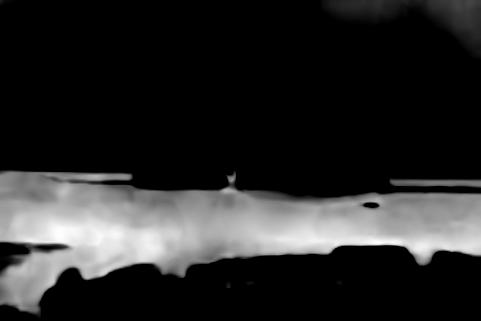

Refer to caption

(a) Original Image

(b) SNIC, DICE 81.6%

(c) EA, DICE 81.3%

(d) Ours, DICE 87.9%

(e) Ground Truth

Figure 7: Qualitative Comparison of Superpixel Algorithms on an image from DeepVess.

The results in Table 1 show that our approach performs best across other superpixel algorithms in an end-to-end segmentation pipeline. Based on this observation we conclude that the slight drop in compactness we observed in the natural image experiments with respect to EA does not affect the quality of post-processing. Moreover, the results stress our method’s robustness with respect to noise. It is also worth noting that it closely matches the performance of a trained neural networkand the second human annotation on this dataset. While the Double-DIP seems to work on natural images with a saliency estimate, it does not converge on noisy microscopic data which is why we decided to stop the optimization after 500 steps. In Figure 7 we can see superpixel based foreground predictions generated from a DeepVess slice. While SNIC fails to match superpixels to vessel structures and overfits to noise artifacts, EA and our method produce smoother superpixels. However, the Deep Decoder is better at detecting low-intensity shapes and adhering to vessel boundaries, as it can be seen around the ground truth objects in the top left part in Figure 7, which is why the segmentation pipeline works best with our method as a superpixel generator.